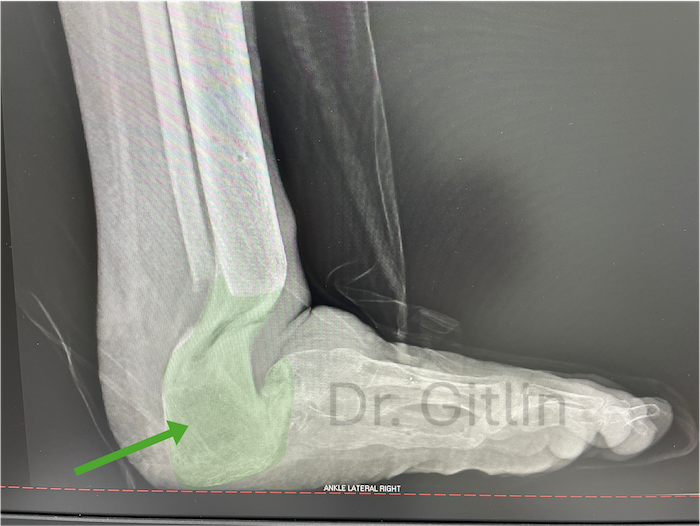

The X-ray below shows in red color the area that we needed to fill with bone. In order to achieve this we cut the leg bone called the tibia and pulled a piece of that bone downward to lengthen the bone and then we turned the bone with the external fixator to replace the heel.

The picture below shows in the green color all of the new bone we created. Even though it will never look like the actual bones and joints it still functions to give the patient a usable limb. Under this X-ray you can see a picture of the patients foot after surgery. The patient is now over two years after surgery and can normally walk and run with his children.